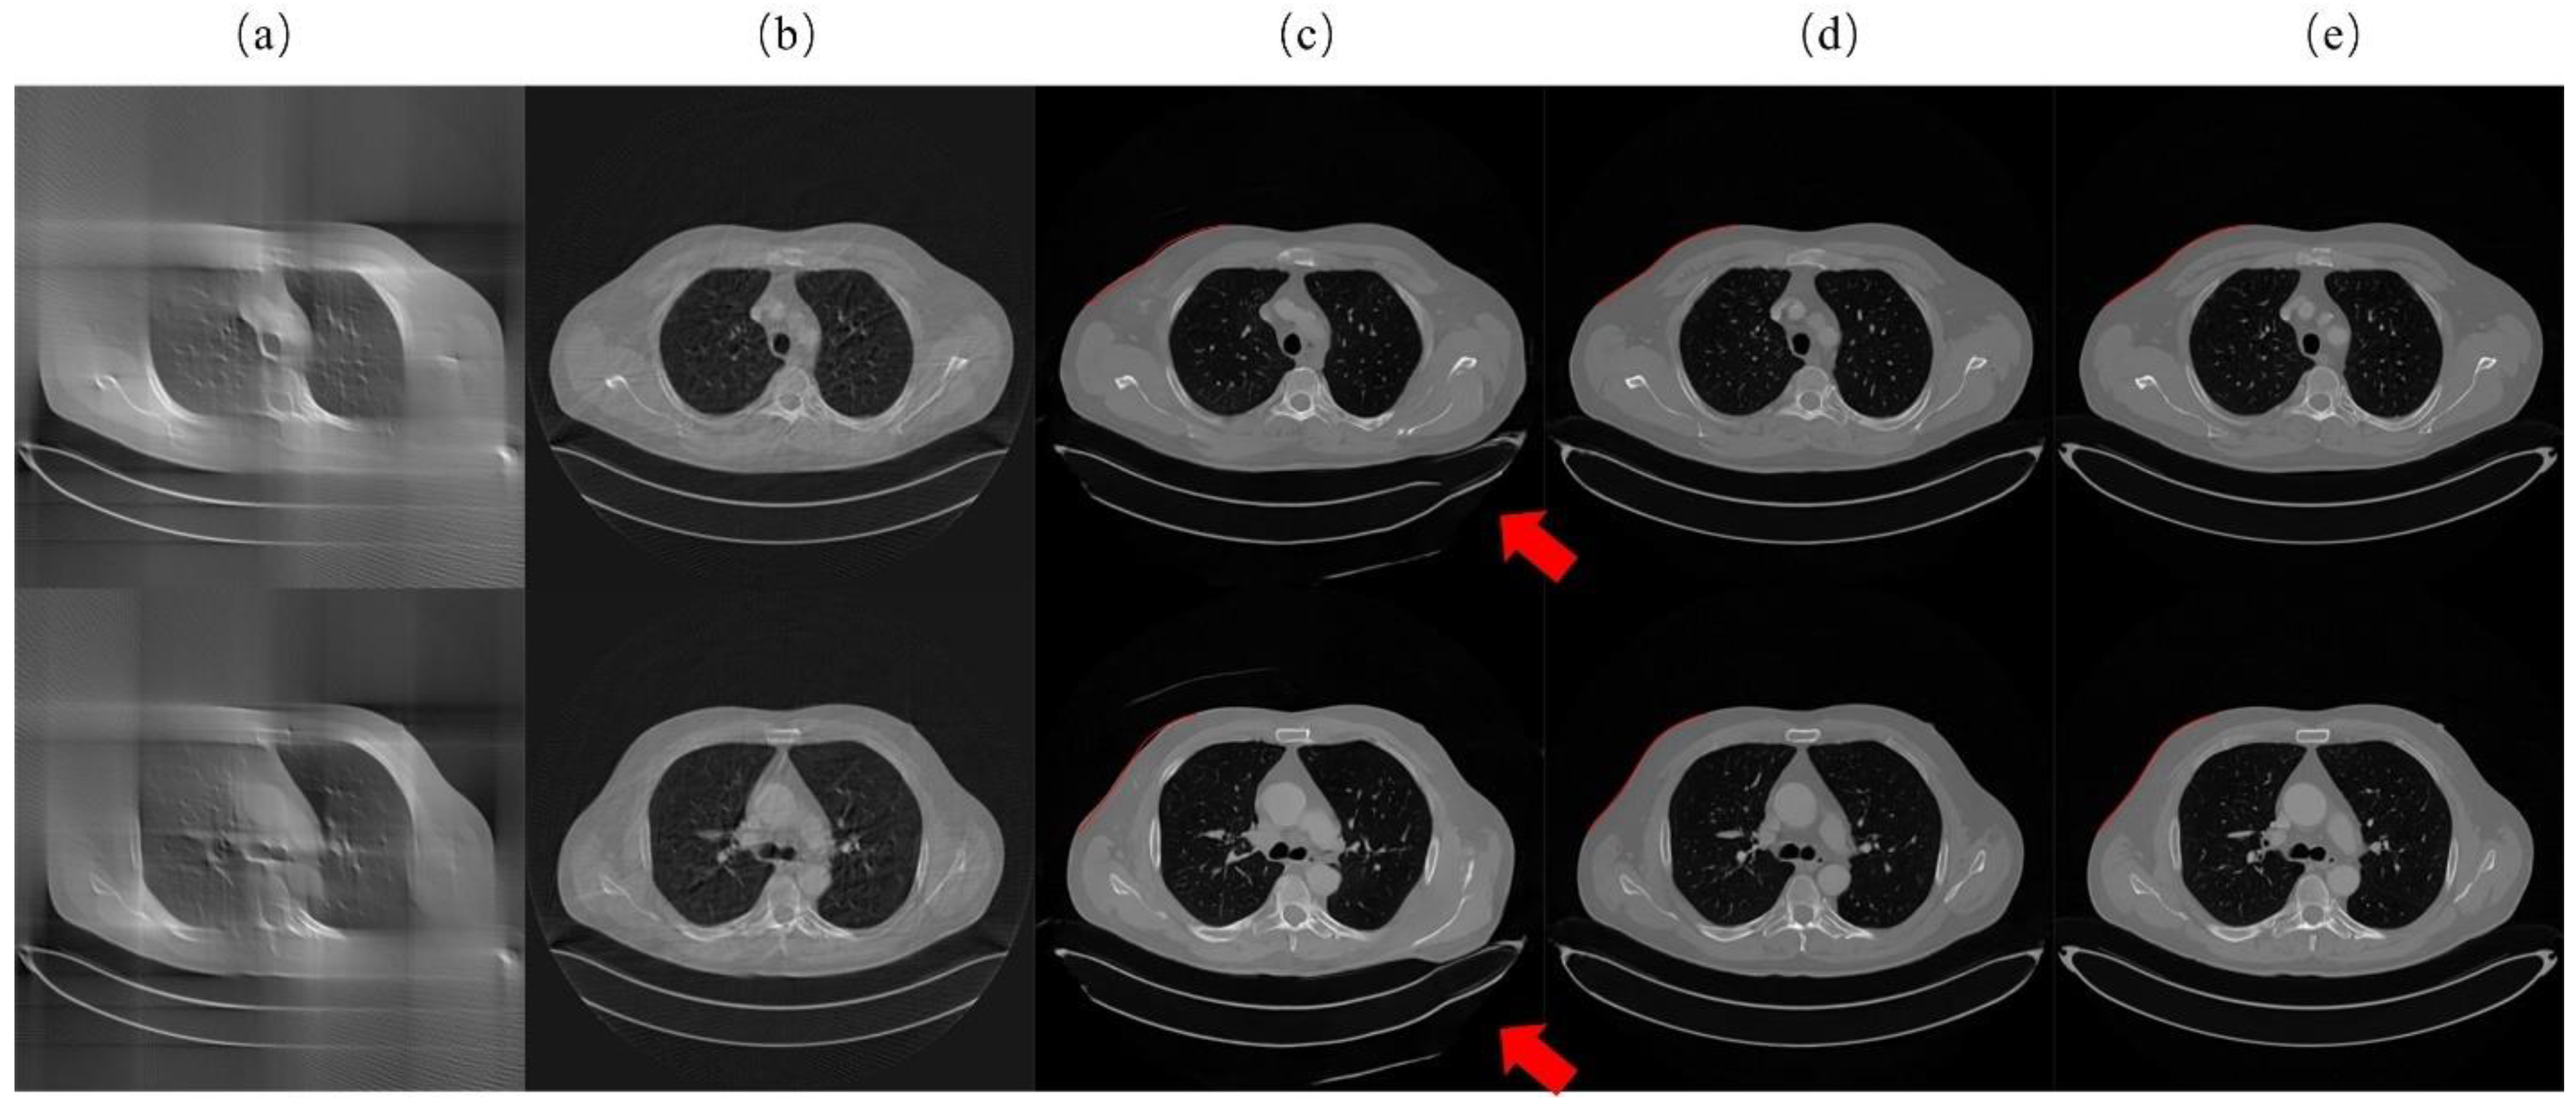

3.2. Qualitative Experimental Results for Lung Data